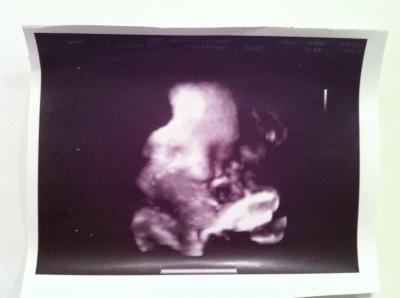

Hallo meine Lieben, so langsam lichtet sich mein Kartonchaos und der Alltag kommt.Hier mal eine kleine Zusammenfassung. Ab Montag gehen meine zwei kleinen dann in die KiTa (wehmütig guck ),die ersten drei Tage geht der Papa mit und dann nur noch mit mir. Ich hab letzten Mittwoch erfolgreich meine Führerscheinprüfung gemeistert und bin nur stolze Führerscheinbesitzering und Fahrerin eines knuddeligen Golf V. Letzten Freitag hatten wir Vorstellung im KH,aber ich denke dort werde ich nicht entbinden,dass einzige was die Hebamme mit (im kath. KH) gefragt hat war,warum ich eine Abtreibung habe machen lassen (Trisomie 18) und ob ich stillen will. Alle Räume waren recht dunkel und eher werniger einladend.Nein danke dann doch lieber etwas weiter fahren. Diesen Freitag war wieder einmal VU,mittlerweile habe ich Wassereinlagerungen in Händen und Beinen (die auch schmerzen),klein Elias wieg nun gut 2600gr und ist 47cm mit 32cm KU.Wehen hab ich auch schon aber die bringen leider nix.MuMu ist weich und fingerdurchlässig,Schleimi fast weg. Ach ja meine KiWa hab ich nun doch im Laden besorgt und in gut einer Woche bekomm ich auch noch die Tasche,mein Männe schiebt schon fleißig in der Wohnung auf und ab . Unsere Babyecke im Schlafzimmer ist auch fast fertig (werd die Tage mal ein Bild machen),da Elias ja die ersten Monate bei uns im Schlafzimmer bleibt So das wars dann erstmal von uns.Anbei das Bild von Freitag mit Fäustchen vorm Mund *hach bin ich verliebt* Lieben Gruß Patricia (37+2) .

Bild zu Ein Lebenszeichen aus dem Kartondschungel - Forum für September - Mamis